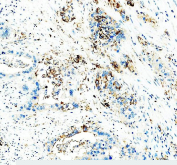

IHC staining of FFPE human teratoma tissue with CD24 antibody, HRP-labeled secondary and DAB substrate. HIER: boil tissue sections in pH8 EDTA for 20 min and allow to cool before testing.

IHC staining of FFPE human appendix tissue with CD24 antibody, HRP-labeled secondary and DAB substrate. HIER: boil tissue sections in pH8 EDTA for 20 min and allow to cool before testing.